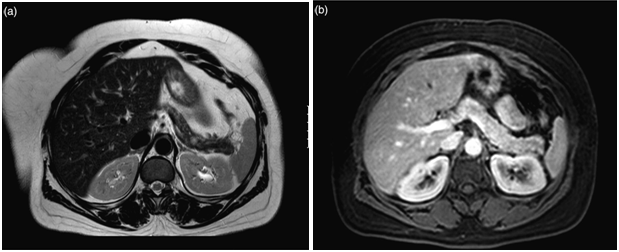

The latest studies have demonstrated that MRI is superior to other preoperative imaging techniques in identifying small pancreatic insulinoma. Its sensitivity ranges from 85% to 95%, in the detection of insulinoma and the determination of the presence of metastases. Using conventional sequences, small insulinoma usually have a low signal on T1-weighted sequences and a high signal on T2-weighted sequences. Some insulinomas containing fibrous tissue may show low signal intensity on both T1- and T2-weighted images. An improvement in MRI technique is the use of diffusion weighted MRI (DWI-MRI) for abdominal imaging. DWI is an MRI technique that detects changes in the molecular diffusion of water in biologic tissues and the valuable role of DWI in the detection of pancreatic tumors has been reported in several studies (Figure 4A), (Figure 4B) & (Figure 5).33–36

Figure 5 Example of the use of MRI in the localisation of insulinoma. (a) T2-weighted image demonstrating a lesion in the tail of the pancreas, less well seen in (b) T1-weighted MRI demonstrating the pancreas in the same patient. 32